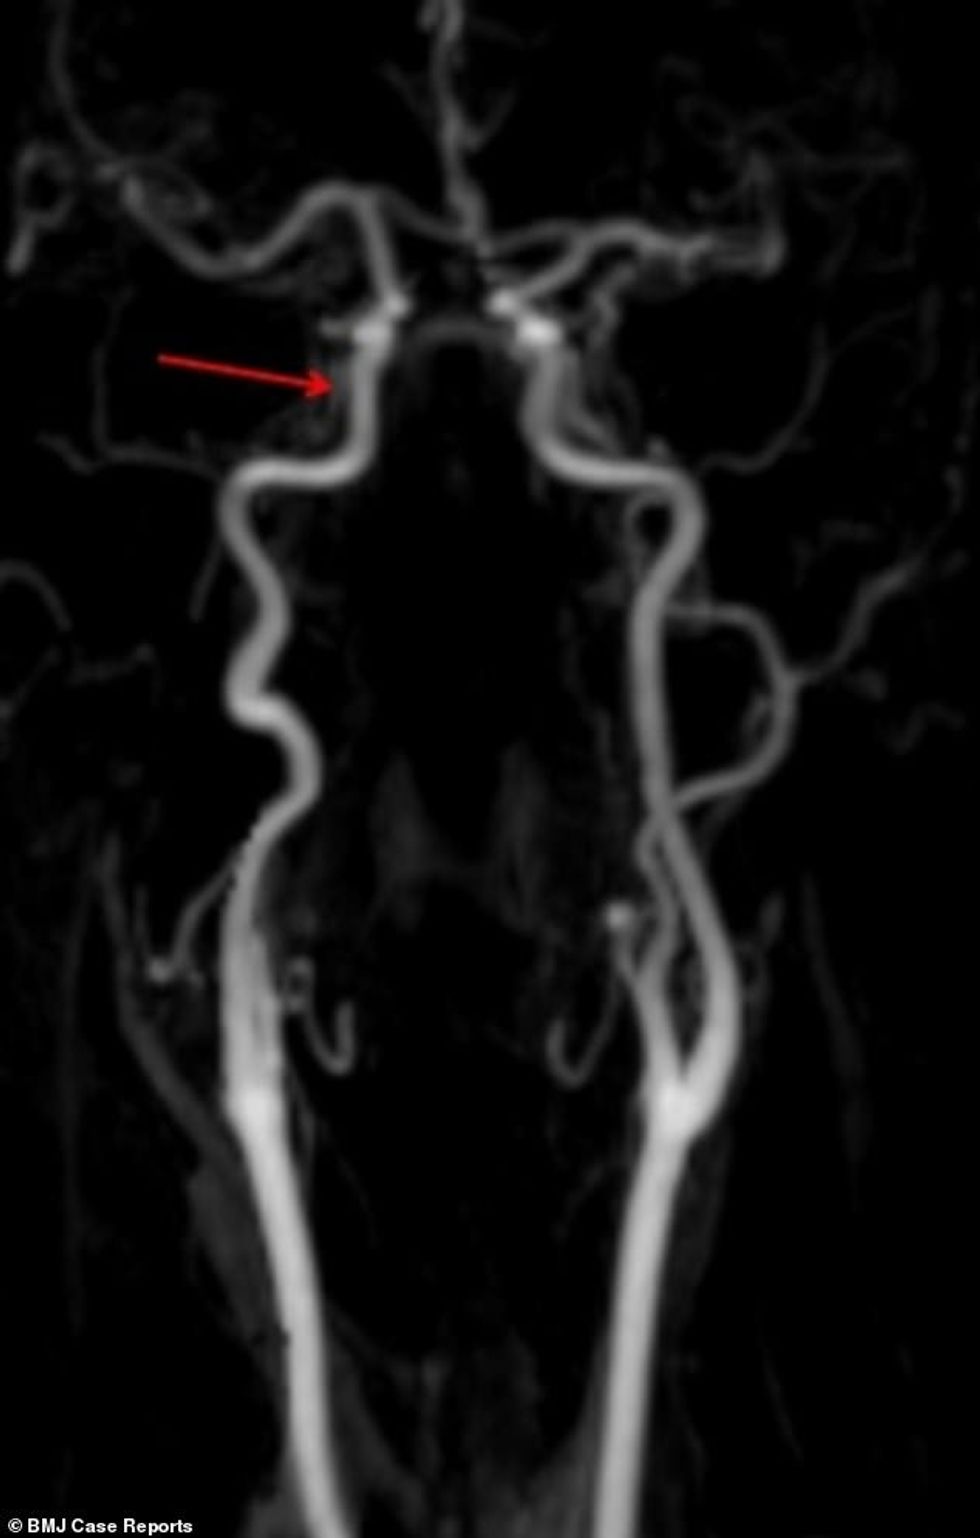

Vizitën e parë e bëri pas dy javësh, kur kapakët e syve po i mbylleshin vet, ndërsa njerëzit i shihte në forma dhe madhësi të ndryshme. Fotografimi me rreze X, ka treguar se i është shkëputur arteria që ia furnizon trurin me gjak dhe oksigjen.